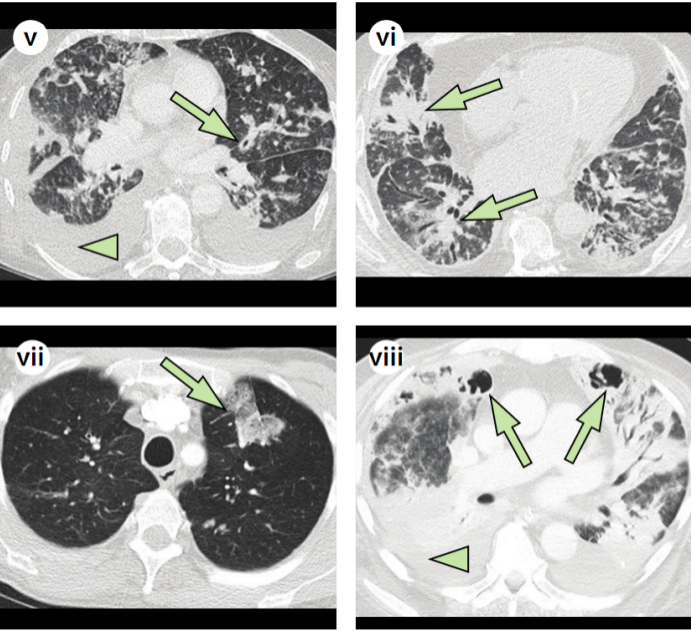

胸部CT(2022-01-10):沿支气管血管束和胸膜下分布的结节影和斑片影(图9)

图片

9  病例2胸部CT